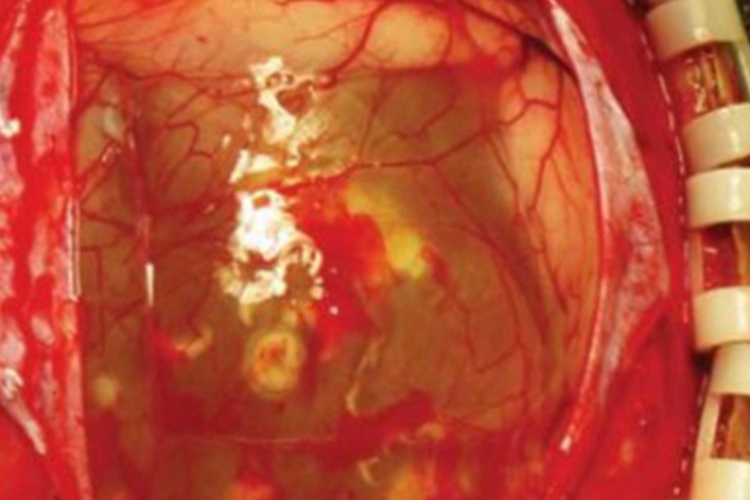

棘球蚴病可发生于头部,检查可见脑膜下散在的几个白色囊肿样物质,并同时存在几条线条状虫体,伴有头痛等不适感。其发展极其缓慢,潜伏期长,从感染至发病为10-20年或更长,多数患者在儿童期感染,成年期发病。